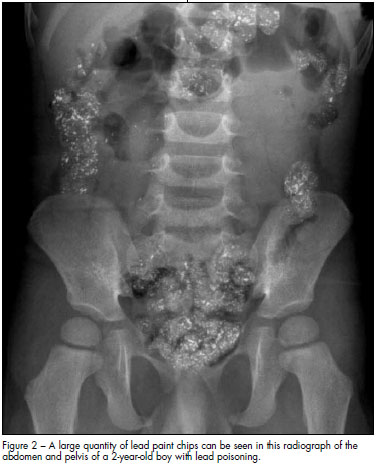

Imaging studies. Abdominal radiography may show the presence of radiopaque flakes, which is a clear indicator of pica (Figure 2). Radiographs of the long bones may show "lead lines."2 Lead lines— which are abnormal calcium deposits, not actual lead deposition—may be detected at the distal metaphysis in children with lead levels greater than 45 µg/dL; these represent growth arrest associated with longterm lead exposure. This radiological finding is not required for diagnosis. Head CT scanning may be needed in patients who present with altered mental status to exclude cerebral edema and structural lesions.